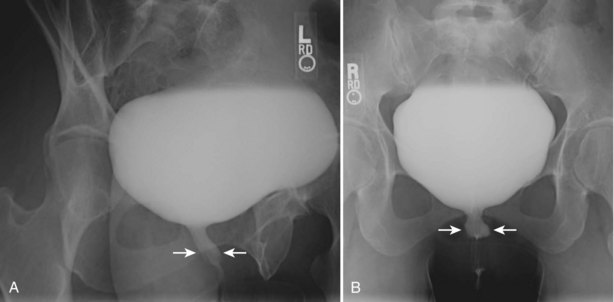

The study may be performed with the patient supine or in a semiupright position using a table capable of bringing the patient into the full upright position. A preliminary pelvic plain radiograph is obtained. In children a 5- to 8-Fr feeding tube is used to fill the bladder to the appropriate volume. Patient comfort should be taken into account when determining the appropriate volume. In the adult population a standard catheter may be placed and the bladder filled to 200 to 400 mL. The catheter is removed and a film is obtained. During voiding, AP and oblique films are obtained. The bladder neck and urethra may be evaluated by fluoroscopy during voiding. Bilateral oblique views may demonstrate low-grade reflux, which cannot be appreciated on the AP film. In addition, oblique films will demonstrate bladder or urethral diverticula, which are not always visible in the straight AP projection. Postvoiding films should be performed (Fig. 4–11).

Figure 4–11 A voiding cystourethrography performed for the evaluation of recurrent urinary tract infection in this female patient. A, An oblique film during voiding demonstrates thickening of the midureteral profile (arrows). B, After interruption of voiding, a ureteral diverticulum is clearly visible extending posteriorly and to the left of the midline (arrows).